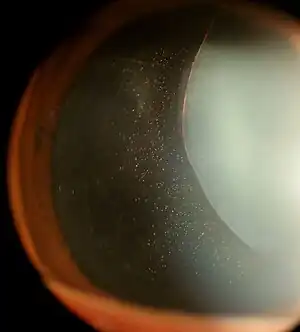

Clinical appearance

The zonules of Zinn are difficult to visualize using a slit lamp, but may be seen with exceptional dilation of the pupil, or if a coloboma of the iris or a subluxation of the lens is present.[8] The number of zonules present in a person appears to decrease with age.[5] The zonules insert around the outer margin of the lens (equator), both anteriorly and posteriorly.[9]